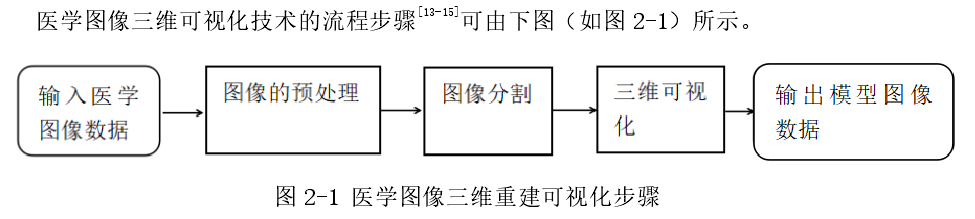

本文基于使用 Opencv、VTK、ITK 和 Qt 工具包,完成了从二维医学图像序列到三维立体器官模型这一过程,并对系统各组成部分的设计与实现进行了详细的介绍。文章中首先介绍了课题研究的背景与意义以及国内外研究现状。接着介绍了三维可视化进程的流程顺序即:读取医学图像序列数据;对读取到的数据进行预处理步骤;对感兴趣的目标器官或组织进行分割;基于分割后的图像数据生成三维立体模型。论文基于每一步的流程详细地介绍了完成这些步骤的相关技术与算法,比如使用区域生长算法分割器官组织以及使用体绘制算法完成三维建模的工作。在介绍完理论技术与算法之后,介绍本系统使用的工具与编写工作环境。比如使用 ITK 工具包完成医学图像读取与图像分割的工作,使用 VTK 工具包完成三维模型的渲染,使用 Qt 完成对整个系统界面的设计以及用户交互事件响应机制的设计,并对系统架构的设计进行了详细介绍。最后通过进行系统测试将本文中提到过的所有算法与技术以截图的形式进行展示。

第二章 医学图像预处理